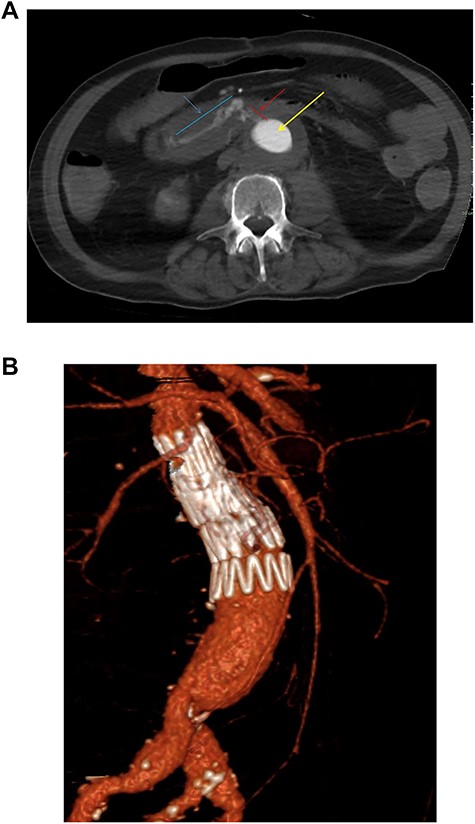

One year after the initial operation, the patient reattended the emergency department with frank haematemesis, rectal bleeding and sepsis in acute haemorrhagic shock. Following resuscitation, an oesophago-gastro duodenoscopy (OGD) revealed fresh blood but no upper GI source of bleeding. Computed tomography (CT) imaging identified a duodenal AEF (Fig. 1a) consistent with communication with the suture line of native aortic-prosthesis. AEF is located 45 mm distal to the lowest (left) branch of the renal artery. The patient successfully underwent emergency relining of the infrarenal aorta into the original graft with a 28 × 43mm COOK® main body extension graft with good overlap (Fig. 1b).

(a) Axial thick slice of a CT with IV contrast in the arterial phase shows the lumen of the surgical graft (yellow arrow), clear contrast opacification within the fistula (red line and arrow) and the duodenum (blue line and arrow) consistent with active haemorrhage; (b) sagittal reconstruction of a CT with IV contrast in the arterial phase showing the overlapping aortic stent grafts inserted to exclude the AEF from the circulation.